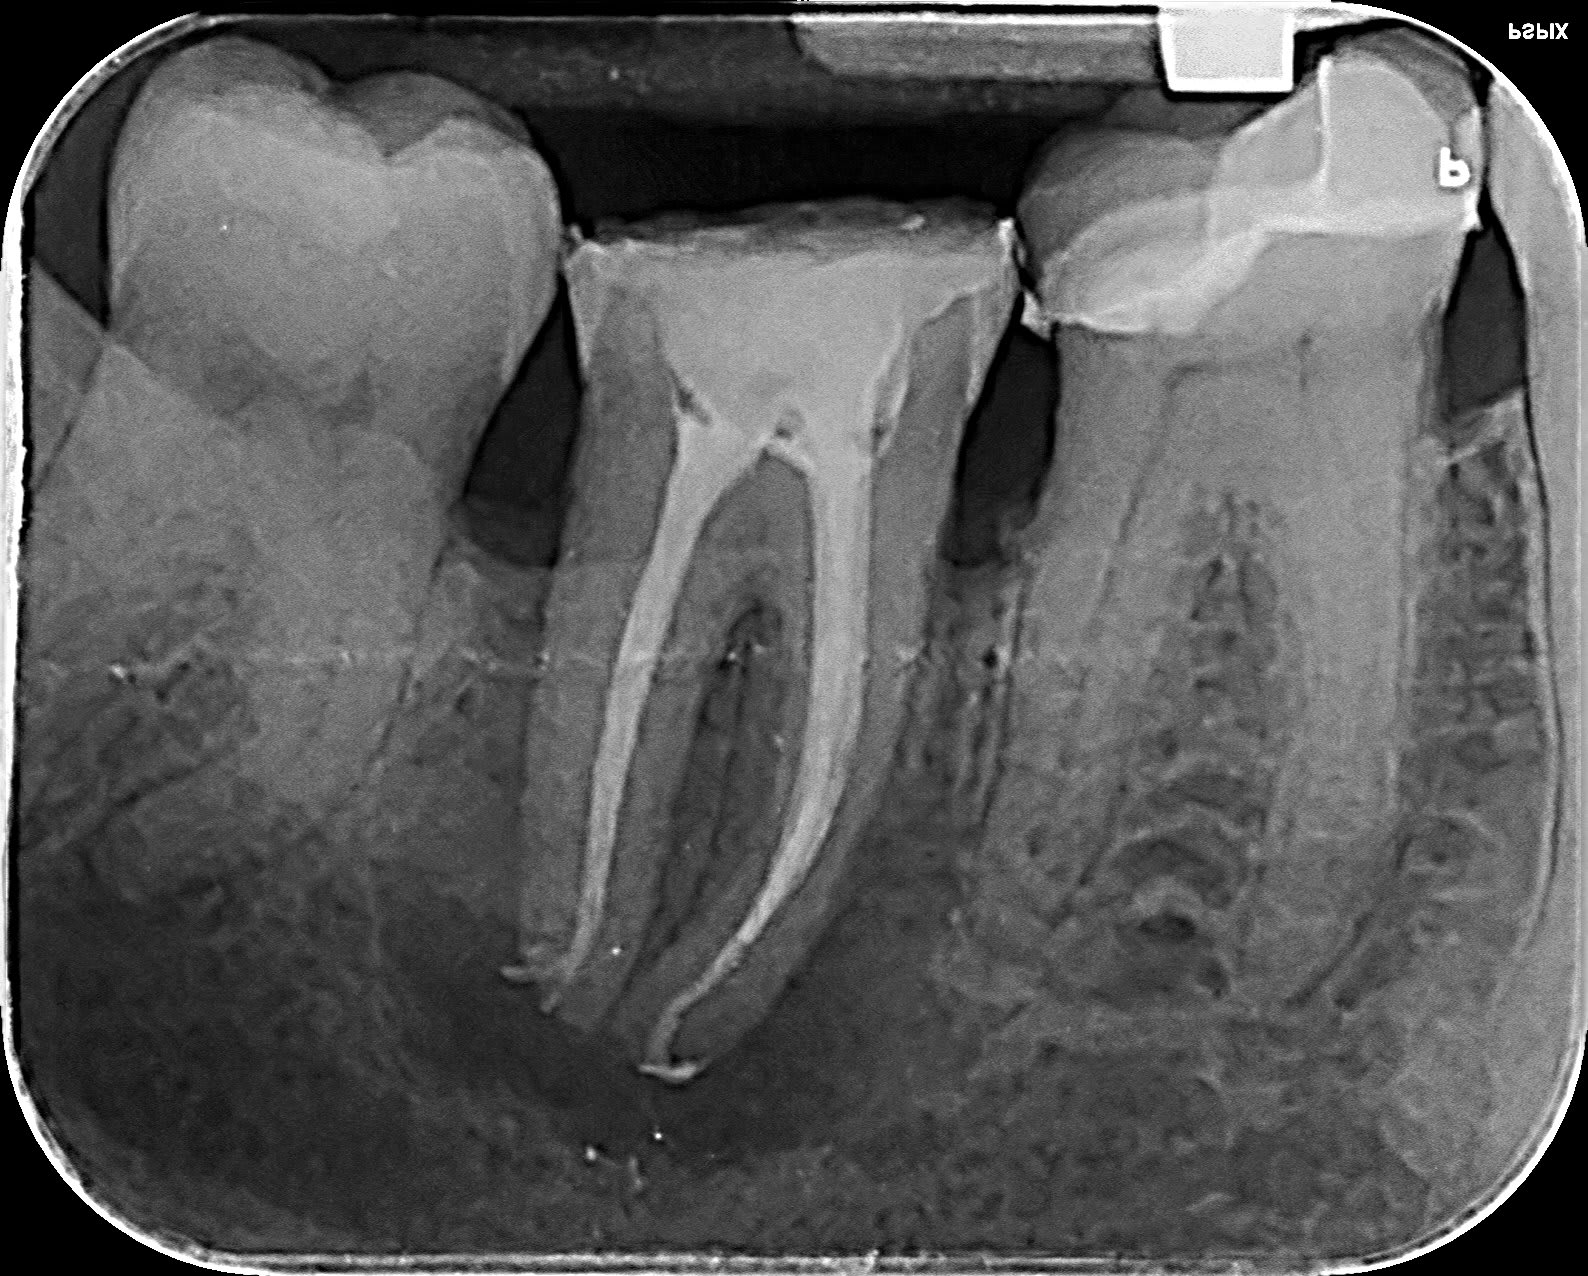

Suite à un échange avec un nonolien... protapers golds, mes pantoufles en endo.

... pour la survie de la dent, on verra...

C'est beau. Mon expérience me dit qu'en l'absence de poche distale, ça survivra. Dans le cas inverse, ça n'a jamais marché pour moi.

Ça ne guérira pas.

bifide.

Elle est réellement bifide? Sur la radio, elle donne bien l'impression de deux canaux en 8, éventuellement avec une large entrée commune.

Deux canaux fusionnés avec séparation avant l'apex comme le montre la radio. C'est aux protapers golds sans instrumentation manuelle.

Tiens tu le crois ça ? Une 26 bifide. Du jamais vu.